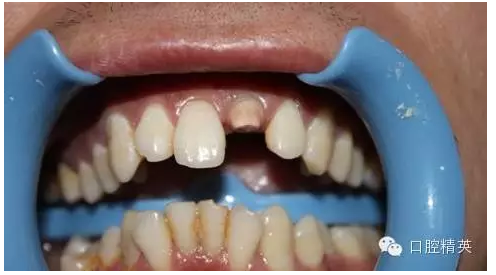

一年輕小伙,在打籃球中,被隊友打斷門牙,來本診所時已經(jīng)露髓,局麻拔髓后,行RCT。后因經(jīng)濟關(guān)系,擬鈷鉻樁加鈷鉻烤瓷冠修復(fù),備牙后才留照片:

術(shù)前 ↑

術(shù)后 ↓

11:正面微笑圖